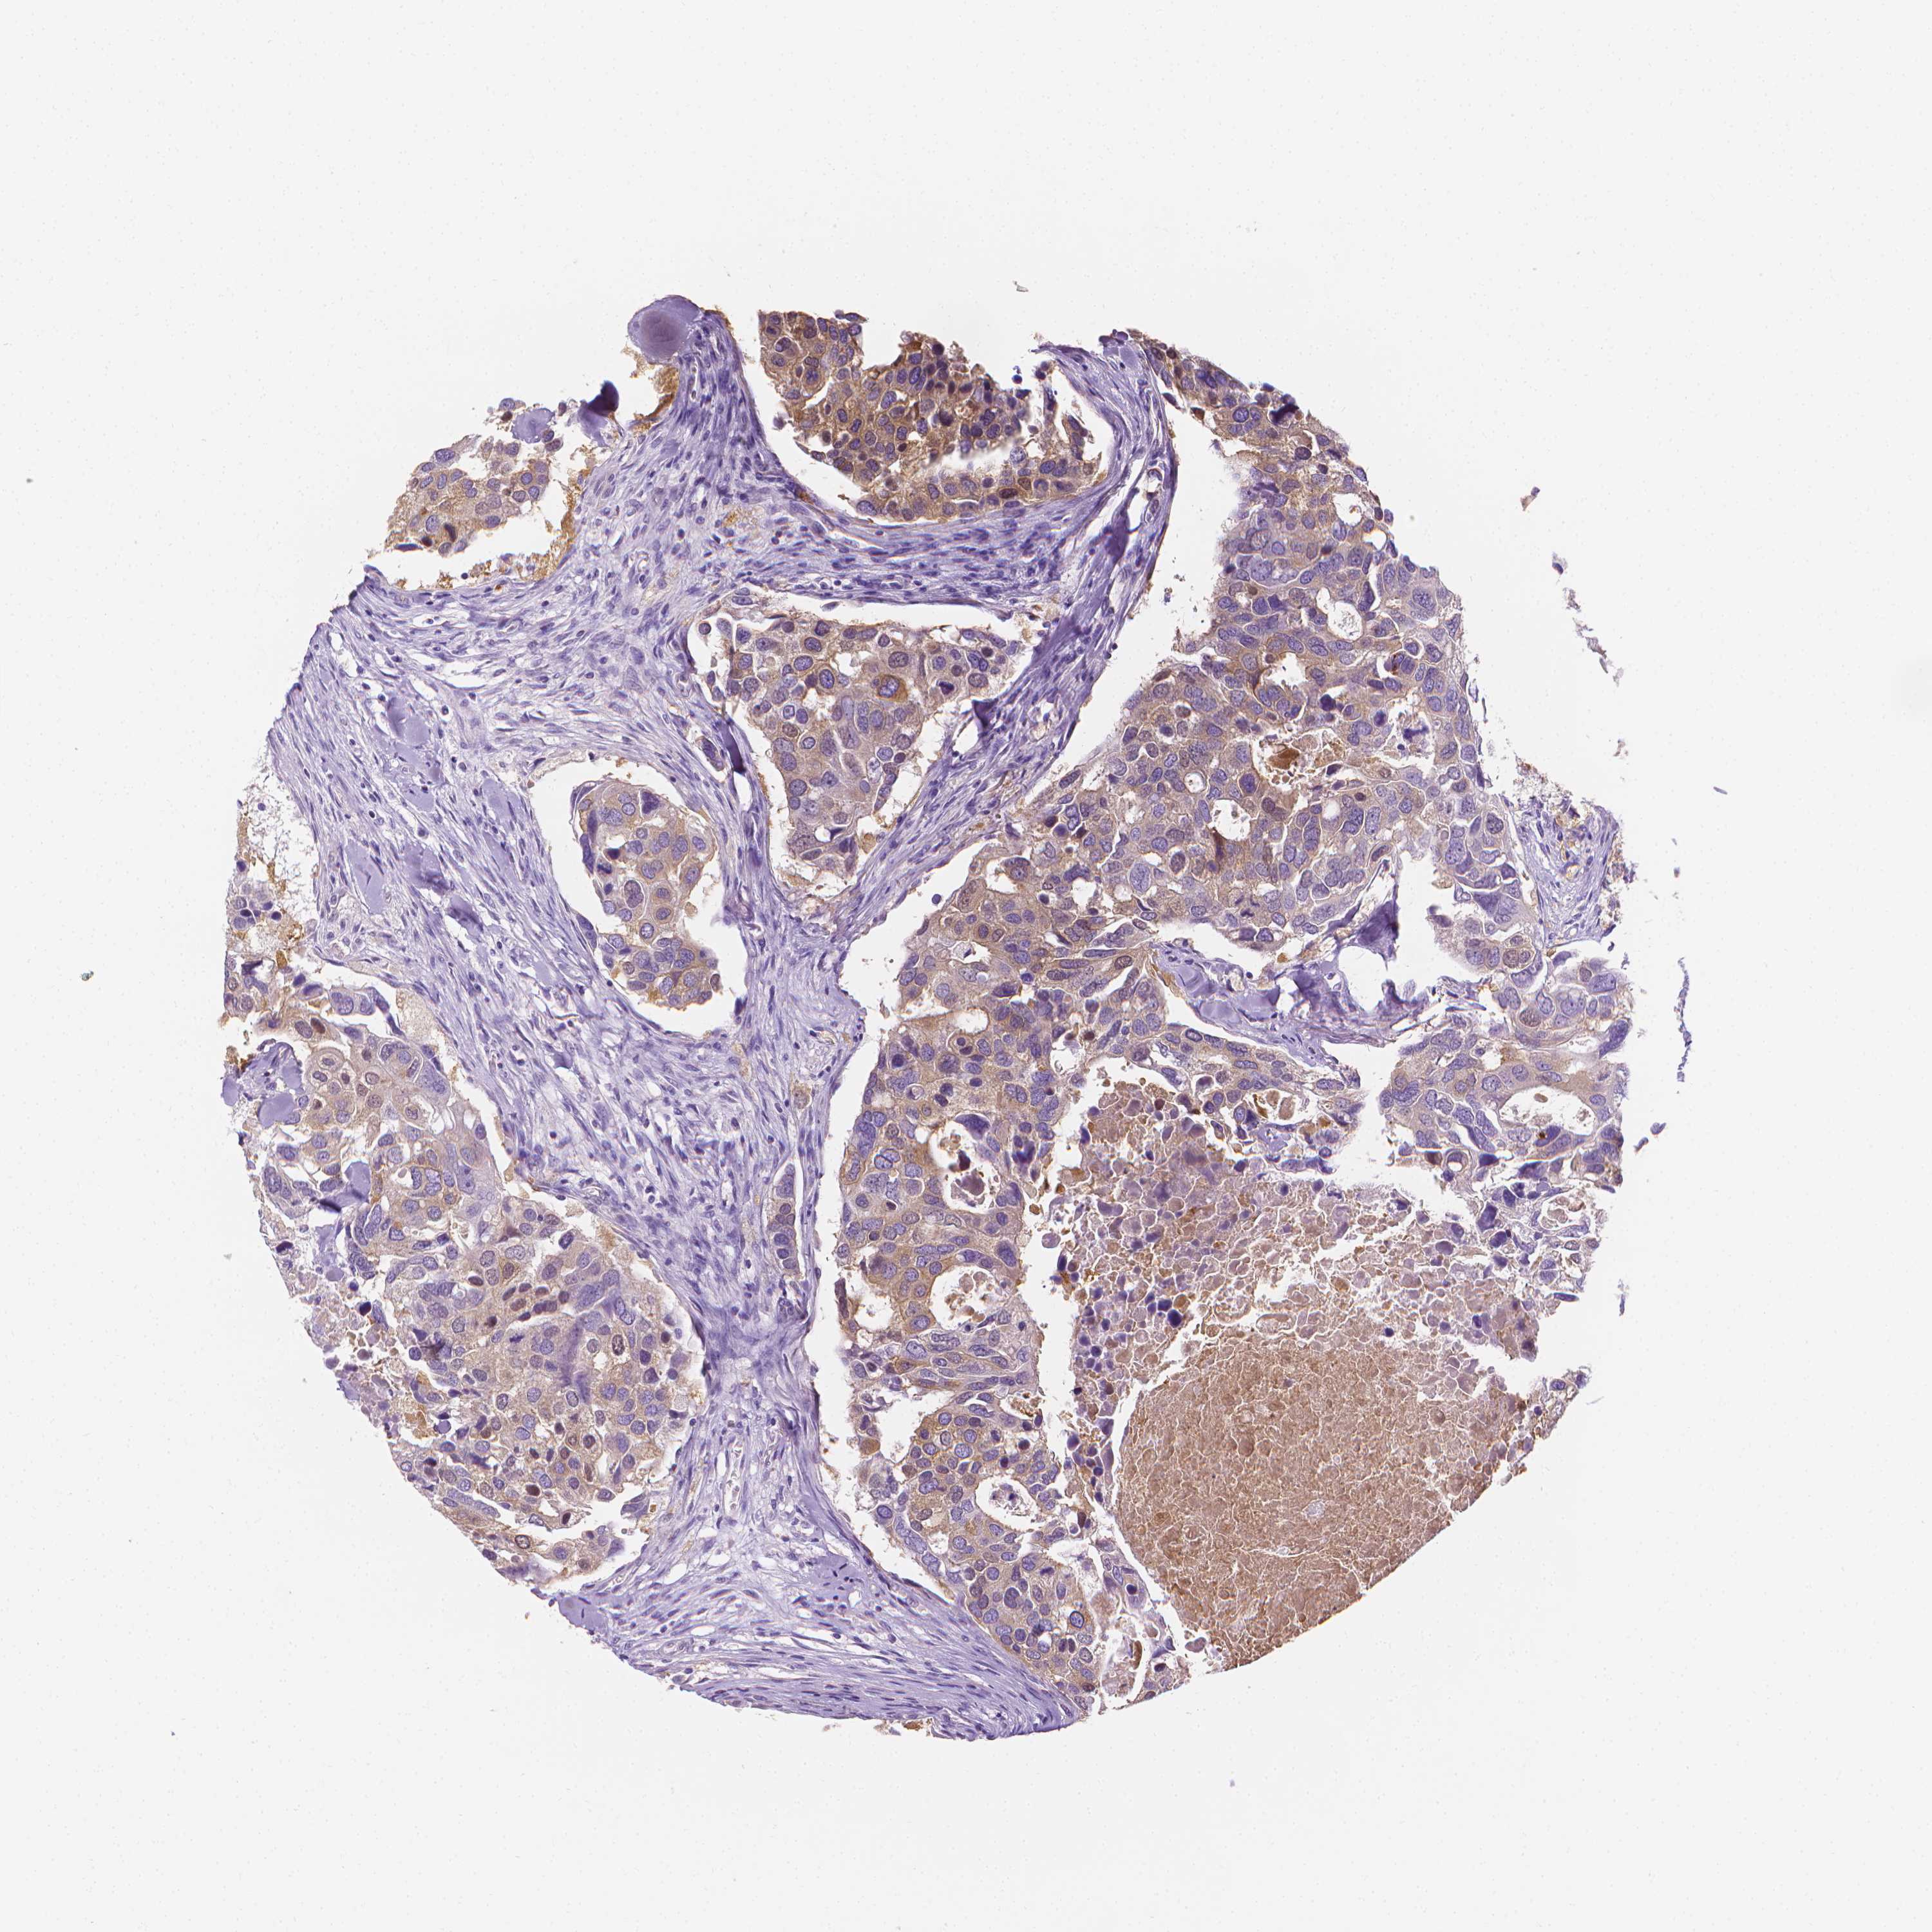

CANCER BREAST CANCER Show tissue menu

BRCA TCGA BRCA VALIDATION PROTEIN EXPRESSION